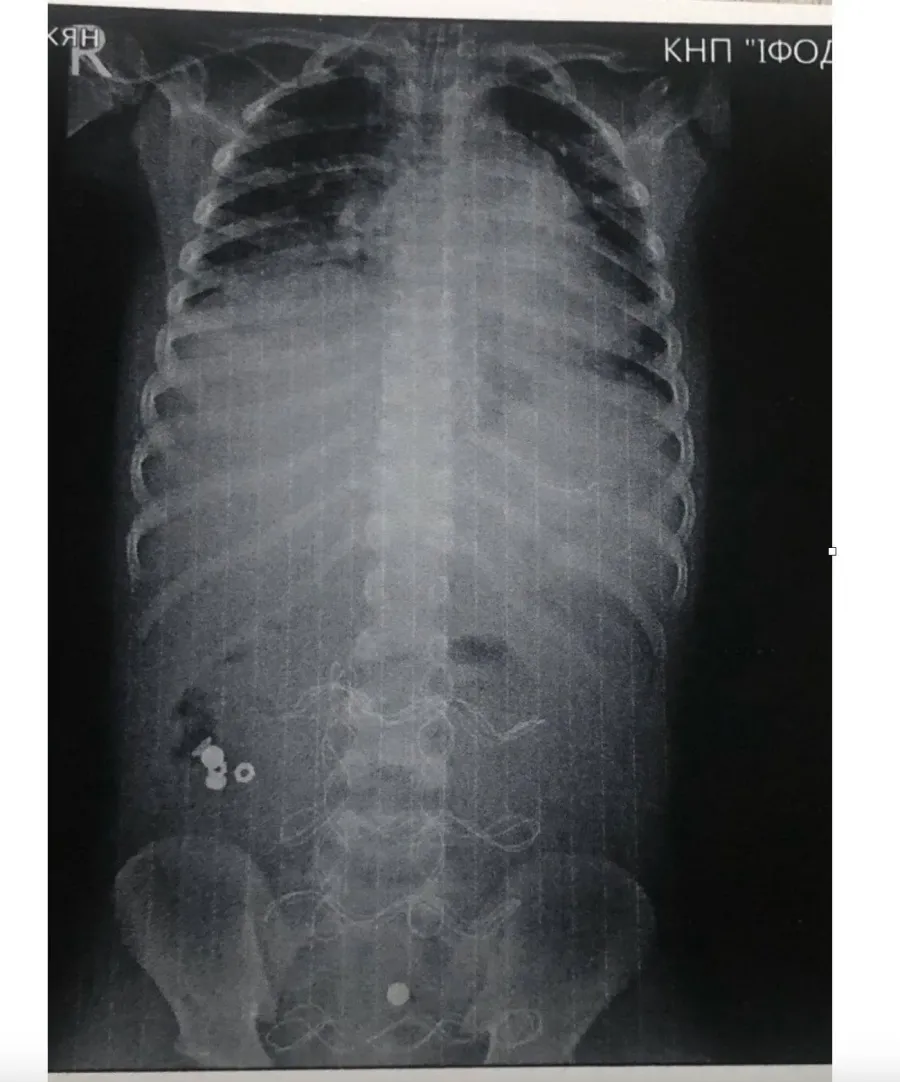

В ОДКЛ привезли 7-річного хлопчика у вкрай тяжкому стані інфекційно-токсичного шоку з клінікою розлитого перитоніту. Як виявилось, все через батарейку, яку дитина проковтнула, що спричинило перфорацію тонкого кишківника.

12 годин тривала передопераційна підготовка. Всього було проведено 3 оперативних втручання і лише на 20 добу дитину було виписано в задовільному стані.